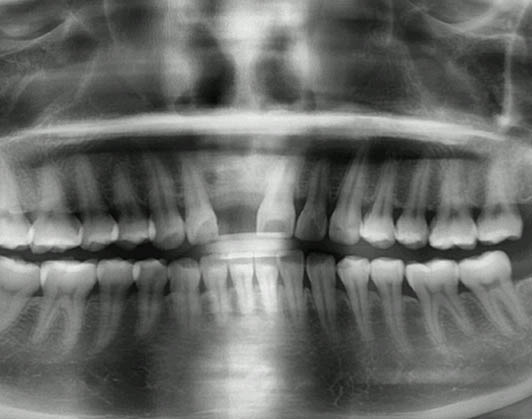

患者:陳先生,來自香港,主要訴求為前牙門牙修復,恢復美觀。

檢查情況:前牙缺失

治療方案:前牙種植修復

選擇種植體:韓國登騰種植體

術前照片